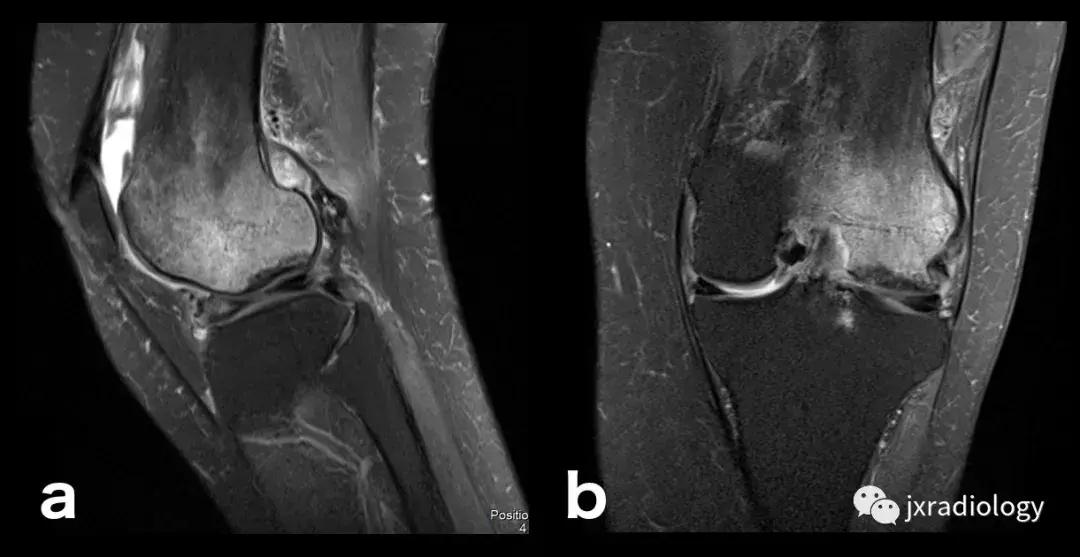

图25:短暂性骨髓水肿综合征(短暂性骨质疏松症):30岁女性急性膝部疼痛的矢状位FS-PDWI MR影像显示骨髓水肿,涉及非负重区域股骨外侧髁骨髓水肿在1年内几乎完全自发消退。短暂性骨髓水肿综合征是自限性病变,其表现为与MRI研究中的骨髓水肿证据相关的关节痛。其病因仍不确定。

图26:局限性游走性骨质疏松症(具有位置变化的短暂性骨髓水肿综合征)(连续冠状PD-FS-WI):在一些情况下,在连续MRI上看到骨髓水肿的位置变化,这被称为局限性游走性骨质疏松症(RMO);尽管可以自愈的短暂性骨髓水肿综合征的情况更为常见,但可以在一小部分病例中转移到不同的关节,或者(甚至更罕见)转移到同一关节内的不同部位(关节内转移) ,如关于该患者所见。在这个关节内RMO病例中,没有创伤史,水肿始于股骨内侧髁,3个月后发现转移到外侧髁。